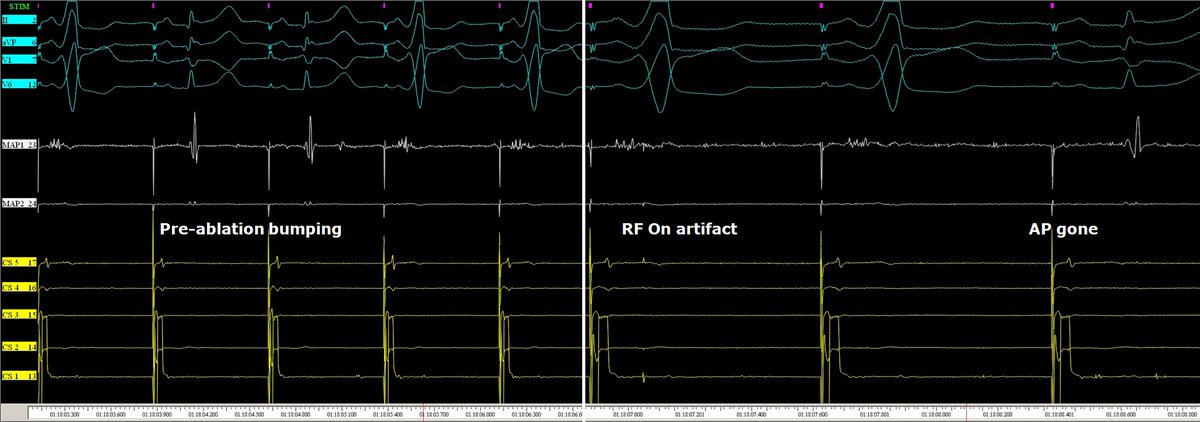

A 58M was referred for redo #ablation of a right anterior para-septal manifest accessory pathway with frequent AVRT episodes. AP gone after careful mapping and about 1 s radiofrequency in the sweet spot.🔥No need for fluoroscopy! #NoFluoro #MapMoreBurnLess #Epeeps

messapus's tweet image. A 58M was referred for redo #ablation of a right anterior para-septal manifest accessory pathway with frequent AVRT episodes. AP gone after careful mapping and about 1 s radiofrequency in the sweet spot.🔥No need for fluoroscopy! #NoFluoro #MapMoreBurnLess #Epeeps